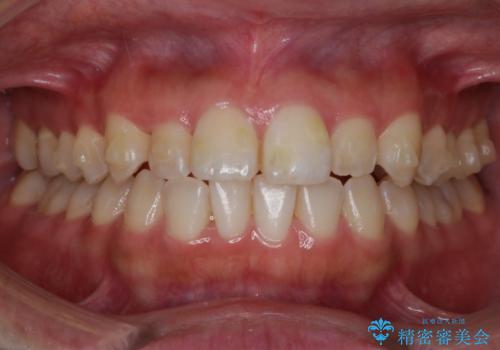

【非抜歯】部分矯正でも治る 前歯の反対咬合

- 前歯にガタつきを主訴にご来院されました。

奥歯の嚙み合わせに問題がほとんどみられなかったため、インビザライン ライトパッケージでの部分矯正を行うこととなりました。

今回のケースでは奥歯の噛み合わせに問題がほぼみられなかったため、前歯の位置のみに焦点を当て部分矯正を行いました。